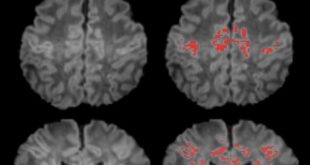

كيف يؤثر تلوث الهواء على نمو دماغ الطفل؟

شام تايمز- متابعة كشفت دراسة علمية حديثة عن وجود ارتباط مقلق بين تعرض النساء الحوامل لتلوث الهواء وتباطؤ نمو الدماغ لدى الأطفال حديثي الولادة، وفقاً …